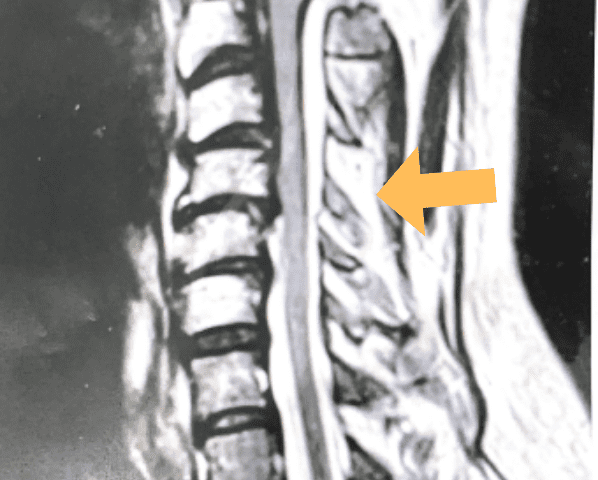

(1b) Hyperintense signal (arrow) at the C3-4 interspinous space consistent with ruptured interspinous ligament,C4-5 (Fig. 1a and 1b).

The fluid was possibly consistent with CSF versus chronic hematoma. The patient was also noted to have a high signal within the interspinous space of C3-C4. This high signal was consistent with a ruptured C3-4 interspinous ligament. Cervical flexion-extension x-rays demonstrated 6 mm of widening of the C3-4 interspinous space on flexion x-ray consistent with cervical instability (Fig. 2a and 2b).